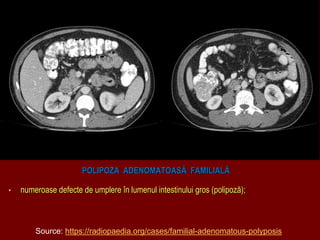

POLIPOZA ADENOMATOASĂ FAMILIALĂ

• numeroase defecte de umplere în lumenul intestinului gros (polipoză);

Source: https://radiopaedia.org/cases/familial-adenomatous-polyposis